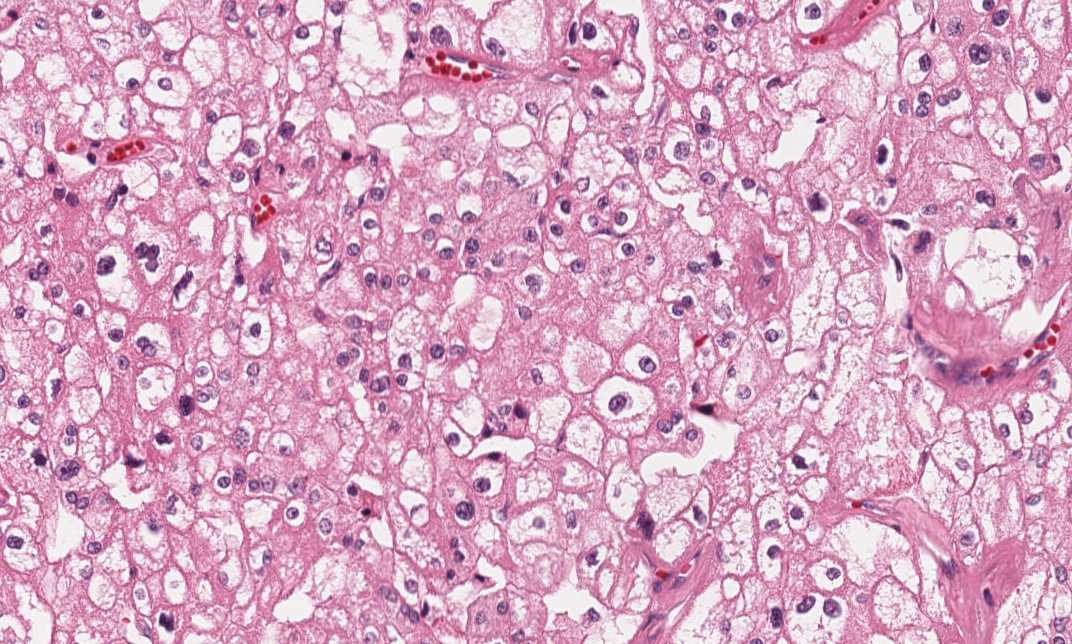

Hematoxylin & eosin

Area 2: Solid sheets of tumor cells with large polygonal tumor cells, distinct cytoplasmic borders, low-grade nuclei and perinuclear halo.

• The tumor (Area B) is composed of solid sheets of neoplastic, large round to polygonal cells with well-defined cell borders and amphophilic to slightly eosinophilic, granular cytoplasm admixed with a small population of polygonal cells with eosinophilic cytoplasm. Perinuclear halo is present in many of the tumor cells. The tumor cells have centrally located, mostly round, low-grade nuclei with small nucleoli.